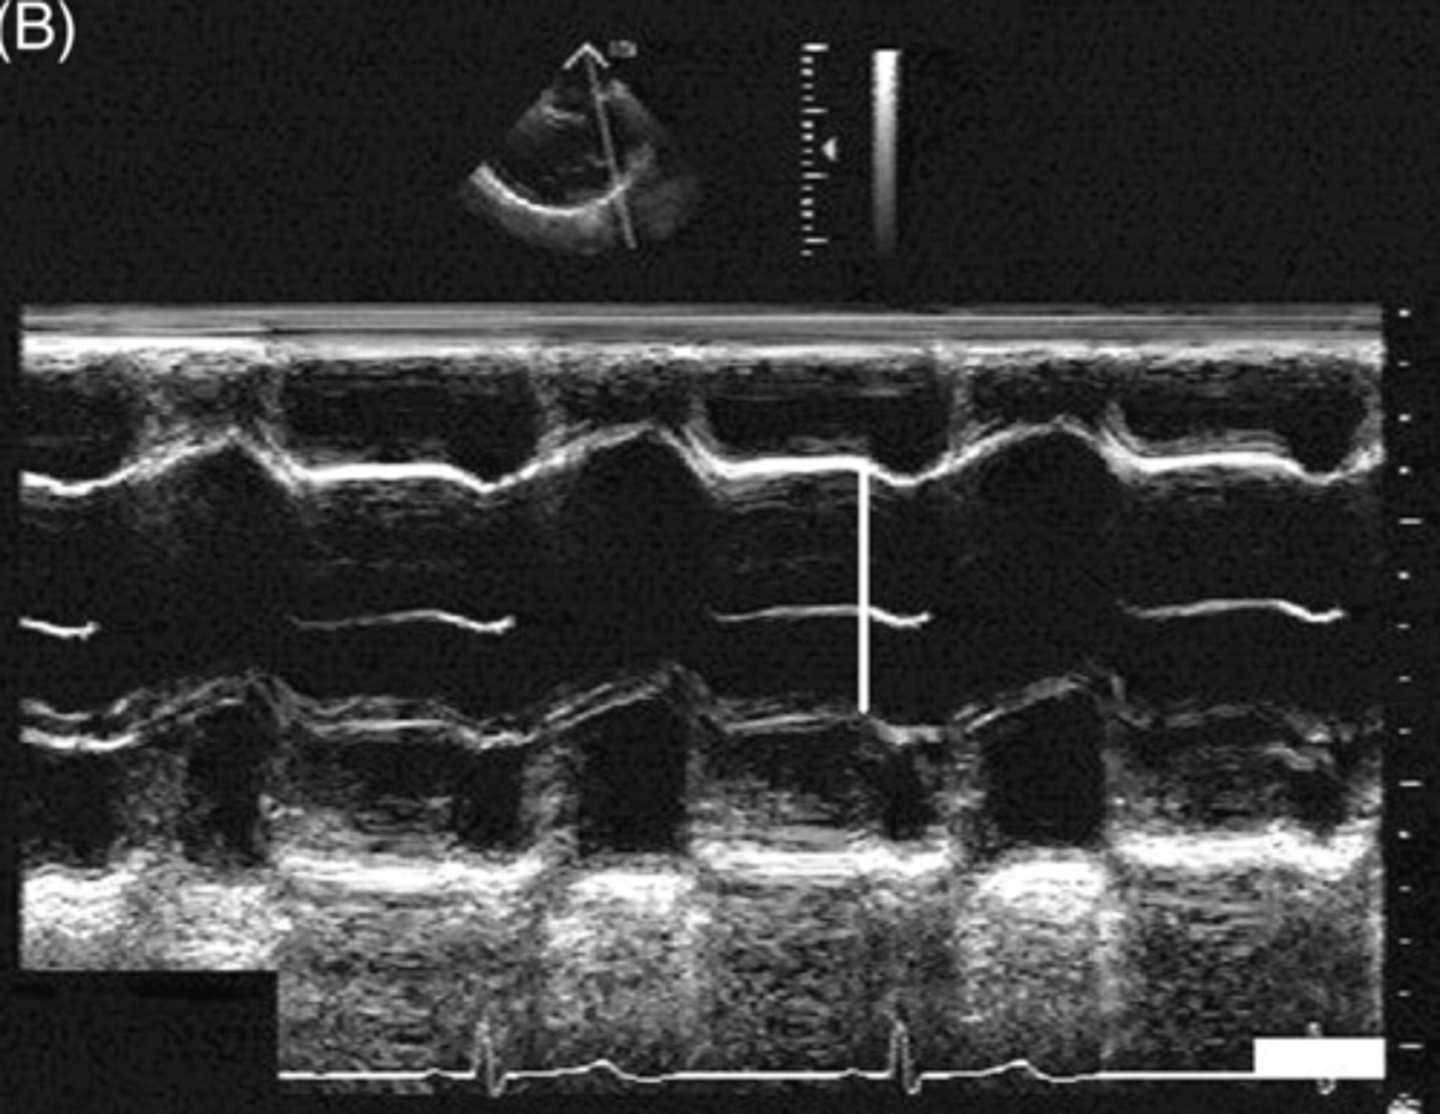

m-mode records _____, ______, and _____

distance, motion, echo strength

___ is measured on the y-axis and ____ is measured on the x-axis

depth; time